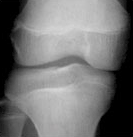

4) 같은 또래 아이들의 키보다 2표준편차 이상 작은 경우에는 성장클리닉 전문의의 진료가 필요합니다. 키가 정확히 또래 아이들보다 작은편인지 큰 편인지 진료를 통해 알아볼 수 있으며 성장판 촬영으로 골연령을 정확히 측정하는 것이 중요합니다.

| 열린경우 | 닫혀가는 경우 | 닫힌 경우 | |

| 경골 Tibia |